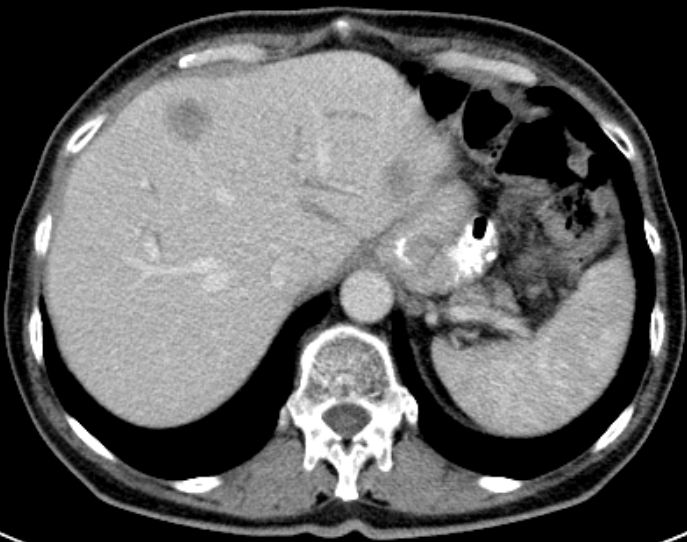

| Leber | 66jährige Frau nach Gastektomie: Lebermetastasen.![]() |

50-jähriger Mann mit primär hepatisch und

pulmonal metastasiertem Antrumkarzinom.![]() | |